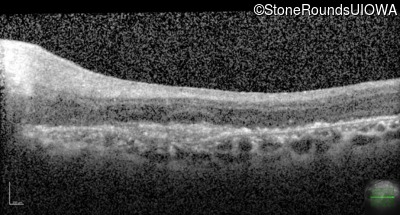

This 43 year old woman first experienced a slight loss of visual acuity at age 23. Fluorescein angiography at that time revealed some vascular leakage from the optic discs and peripheral retina. The maximum combined response of the ERG revealed a selective loss of the b-wave.

Age at visit: 43 years (Visit 2)